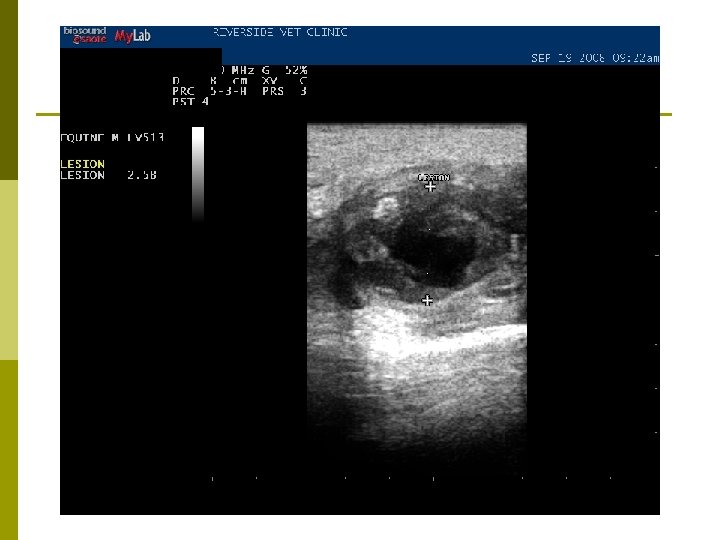

Diagnosis p Index of suspicion p Culture n Gold standard p Ultrasonography p Serology n Internal abscesses

Ultrasonography

Treatment p Time n n “You want me to. . . wait? !” Yeah… p p lets allow the abscess to “cook” for a bit Drainage n Ultrasound guidance p Determine vascularity, depth, site